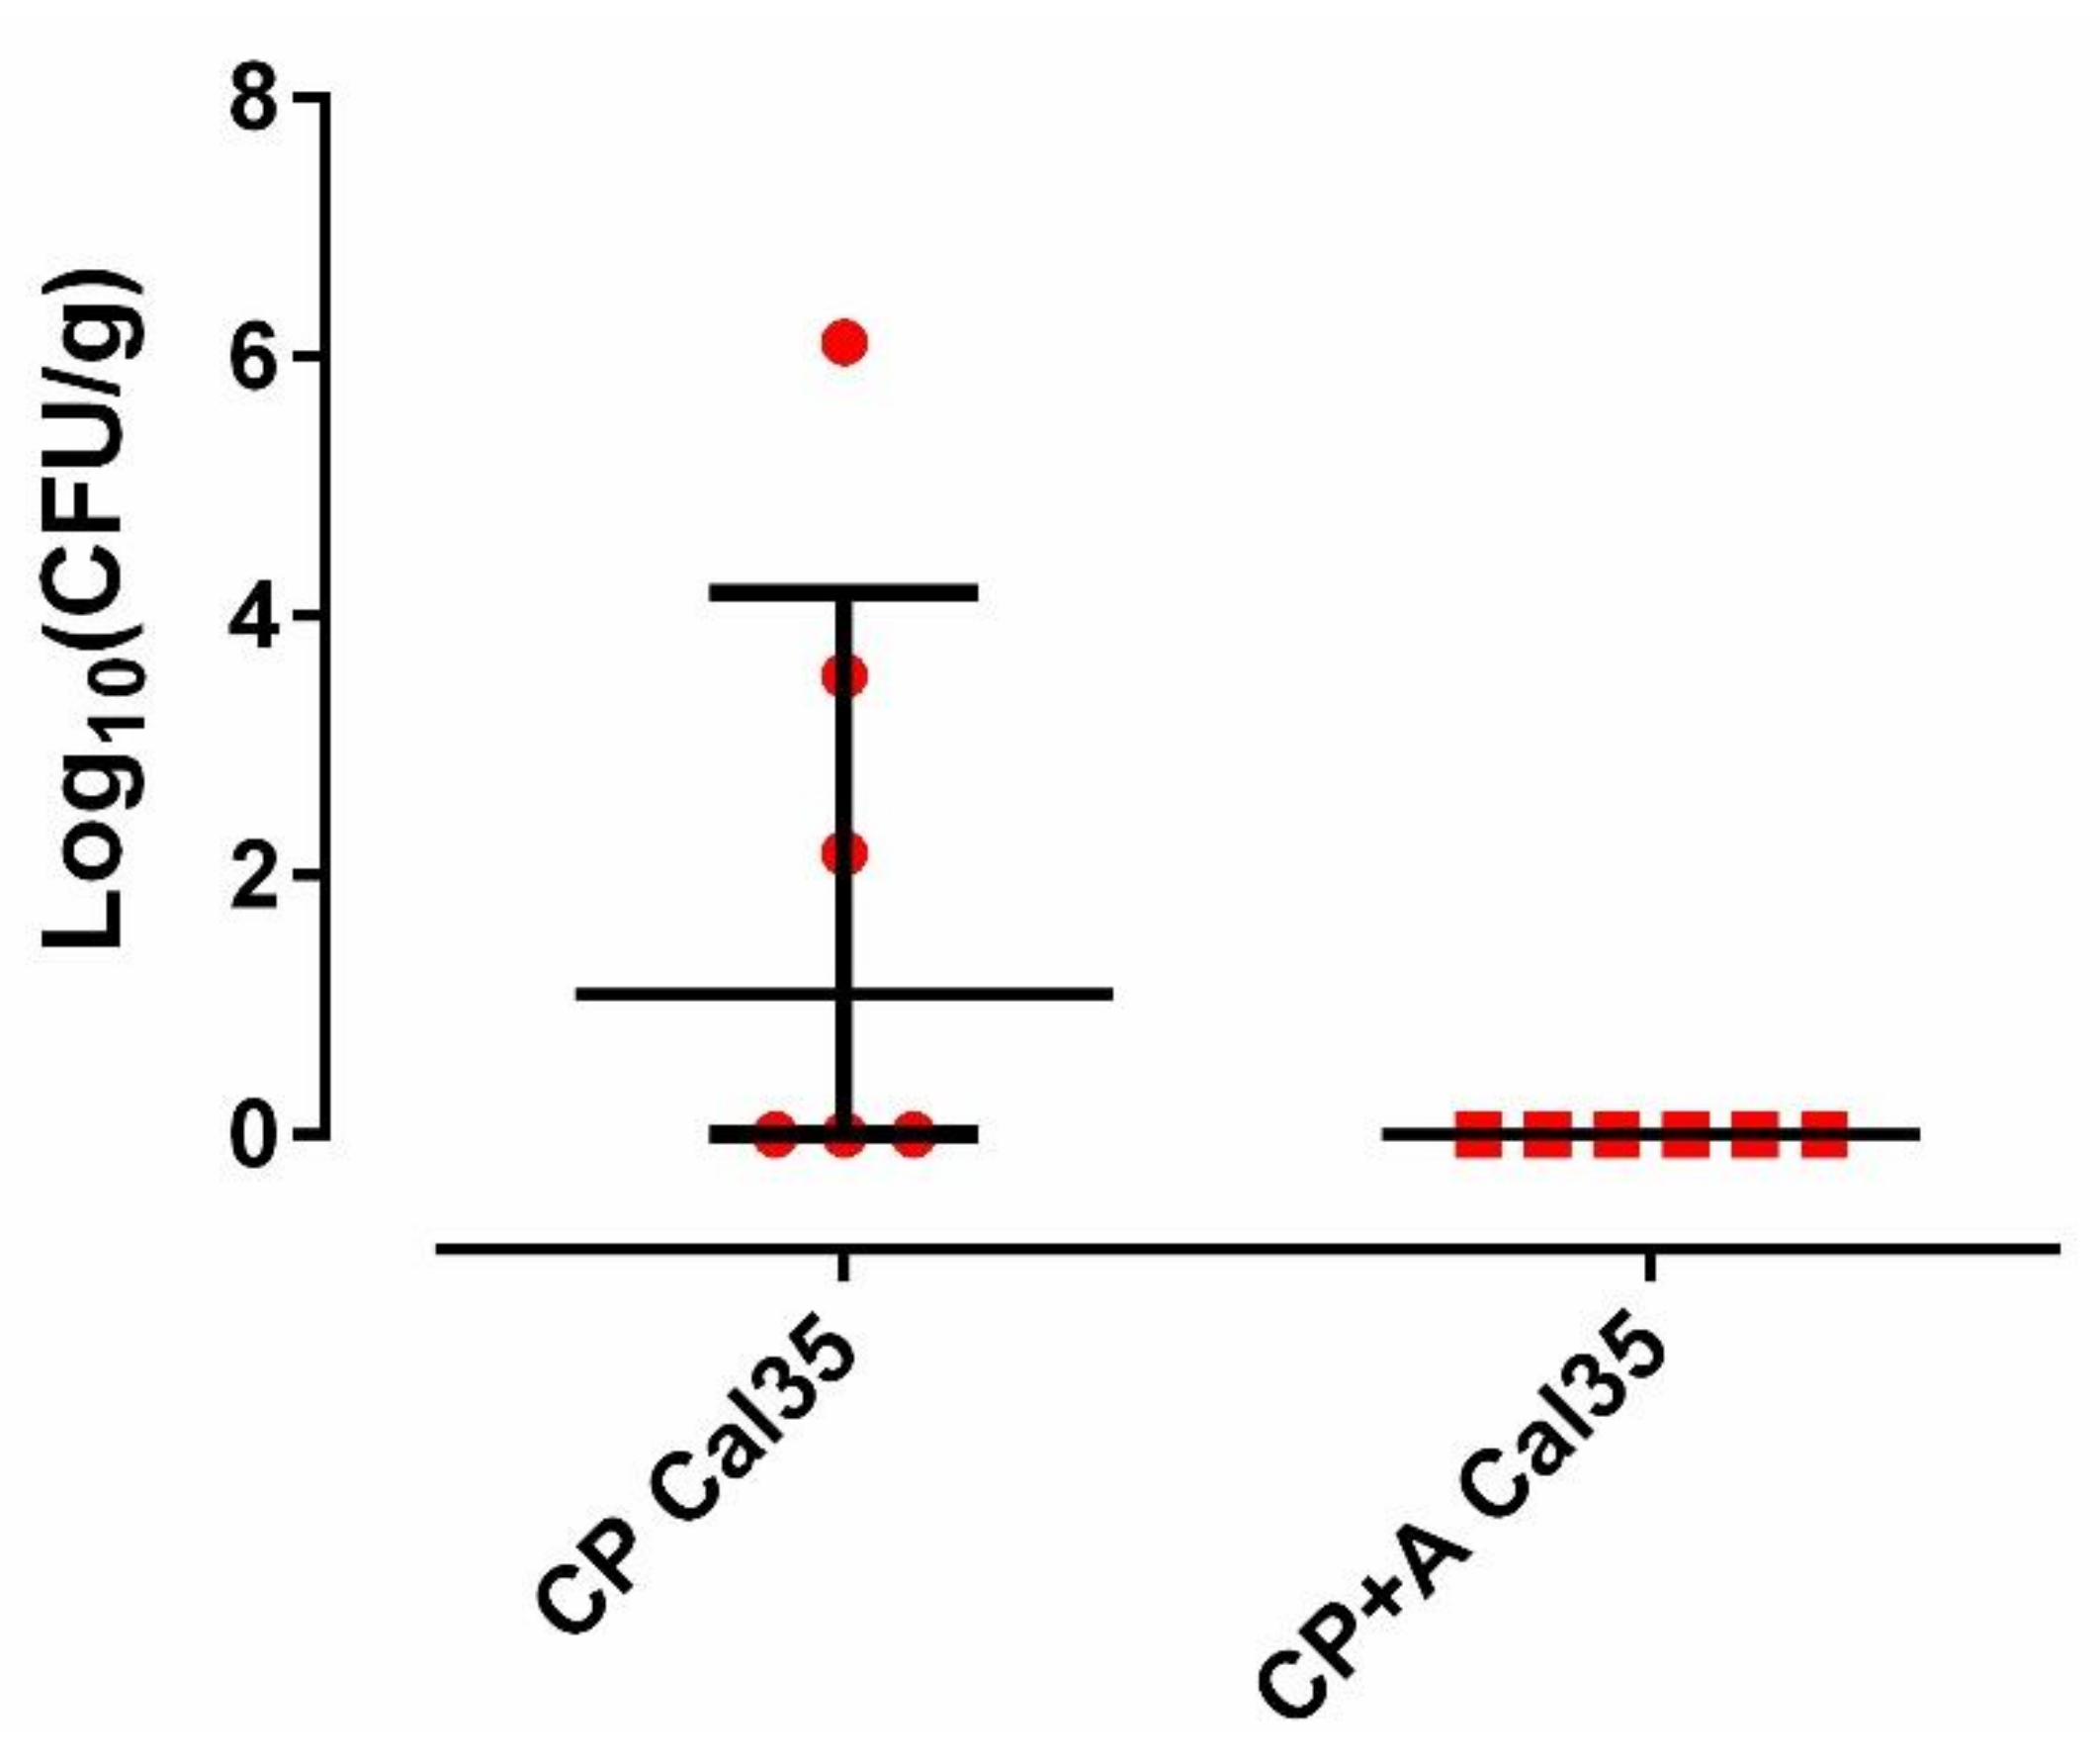

2.2. Microbiological and Pathological Results

4.3. Microbiological and Pathological Studies